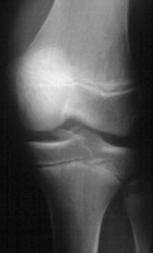

This is a 14 year old male who presented to the emergency room complaining of left knee pain after falling off his bicycle. Examination reveals a swollen left knee. The skin was intact. There was tenderness to palpation diffusely about the knee. Valgus stress at full extension and at 30 degrees revealed an increased laxity on the left. Anterior draw and Lachman tests were also asymmetric with an increased excursion on the left. Neurovascular exam was unremarkable.

This fracture would be best classified as a Type III Meyer's / McKeever tibial spine fracture.

If closed reduction is attempted the knee should be immobilized in 30 degrees of flexion since the etiology of the fracture is hyperextension.

Non-unions are a major problem for these fractures if they are not adequately reduced.

To fully evaluate this fracture prior to treatment an MRI should be obtained.